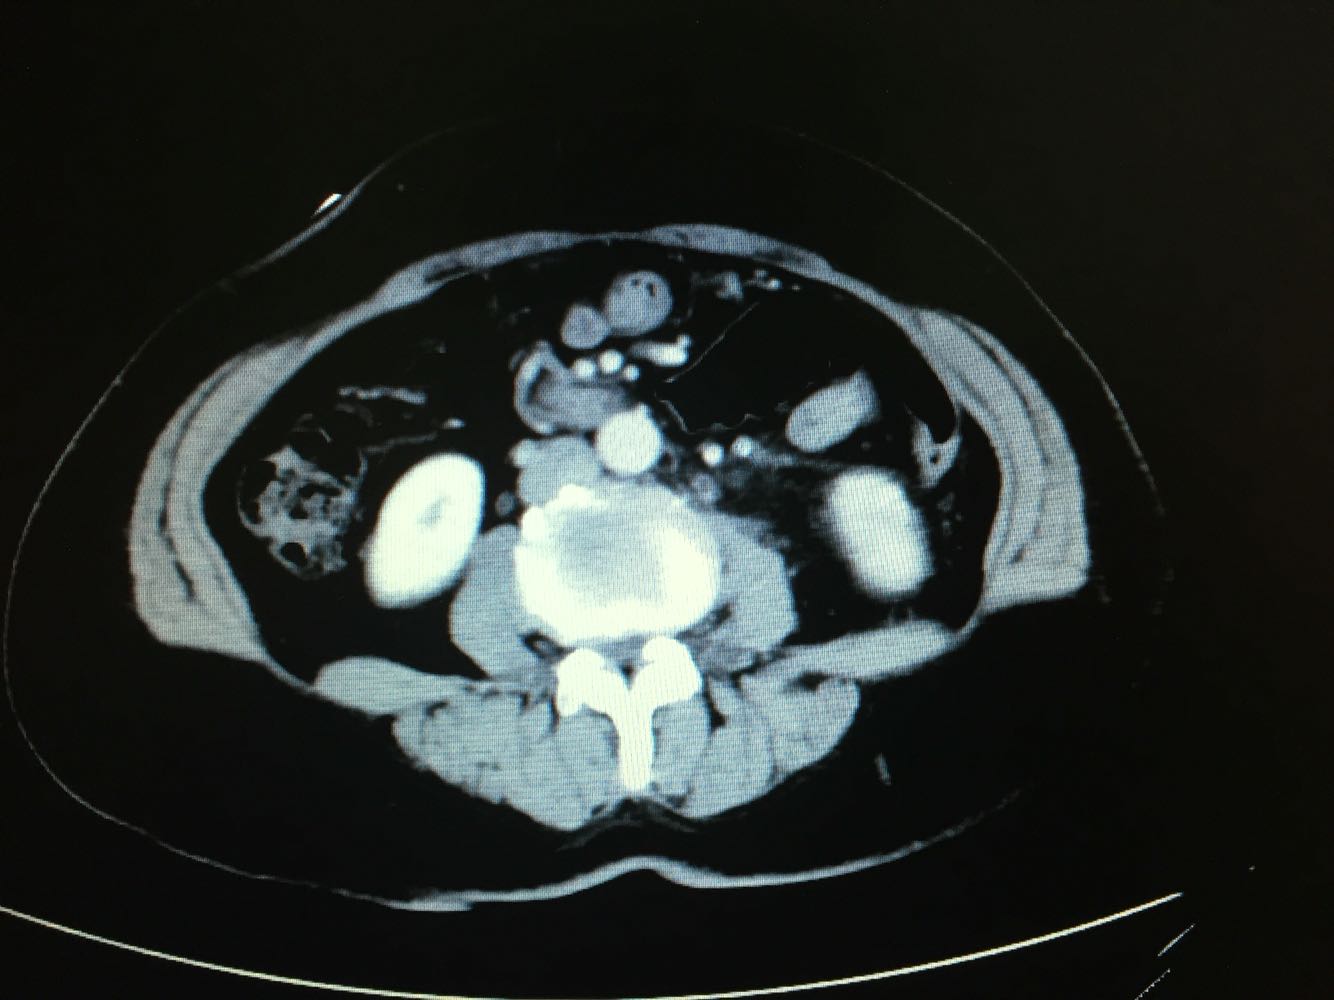

CT提示,左侧肾门处雪人样占位,包裹左肾静脉,左肾积水,与胰腺及左肾关系密切,血常规,肝肾功未见明显异常,GFR左侧27,右侧58。

诊断,左侧腹膜后占位:淋巴瘤?或者淋巴样增生?,侵犯周围器官组织?